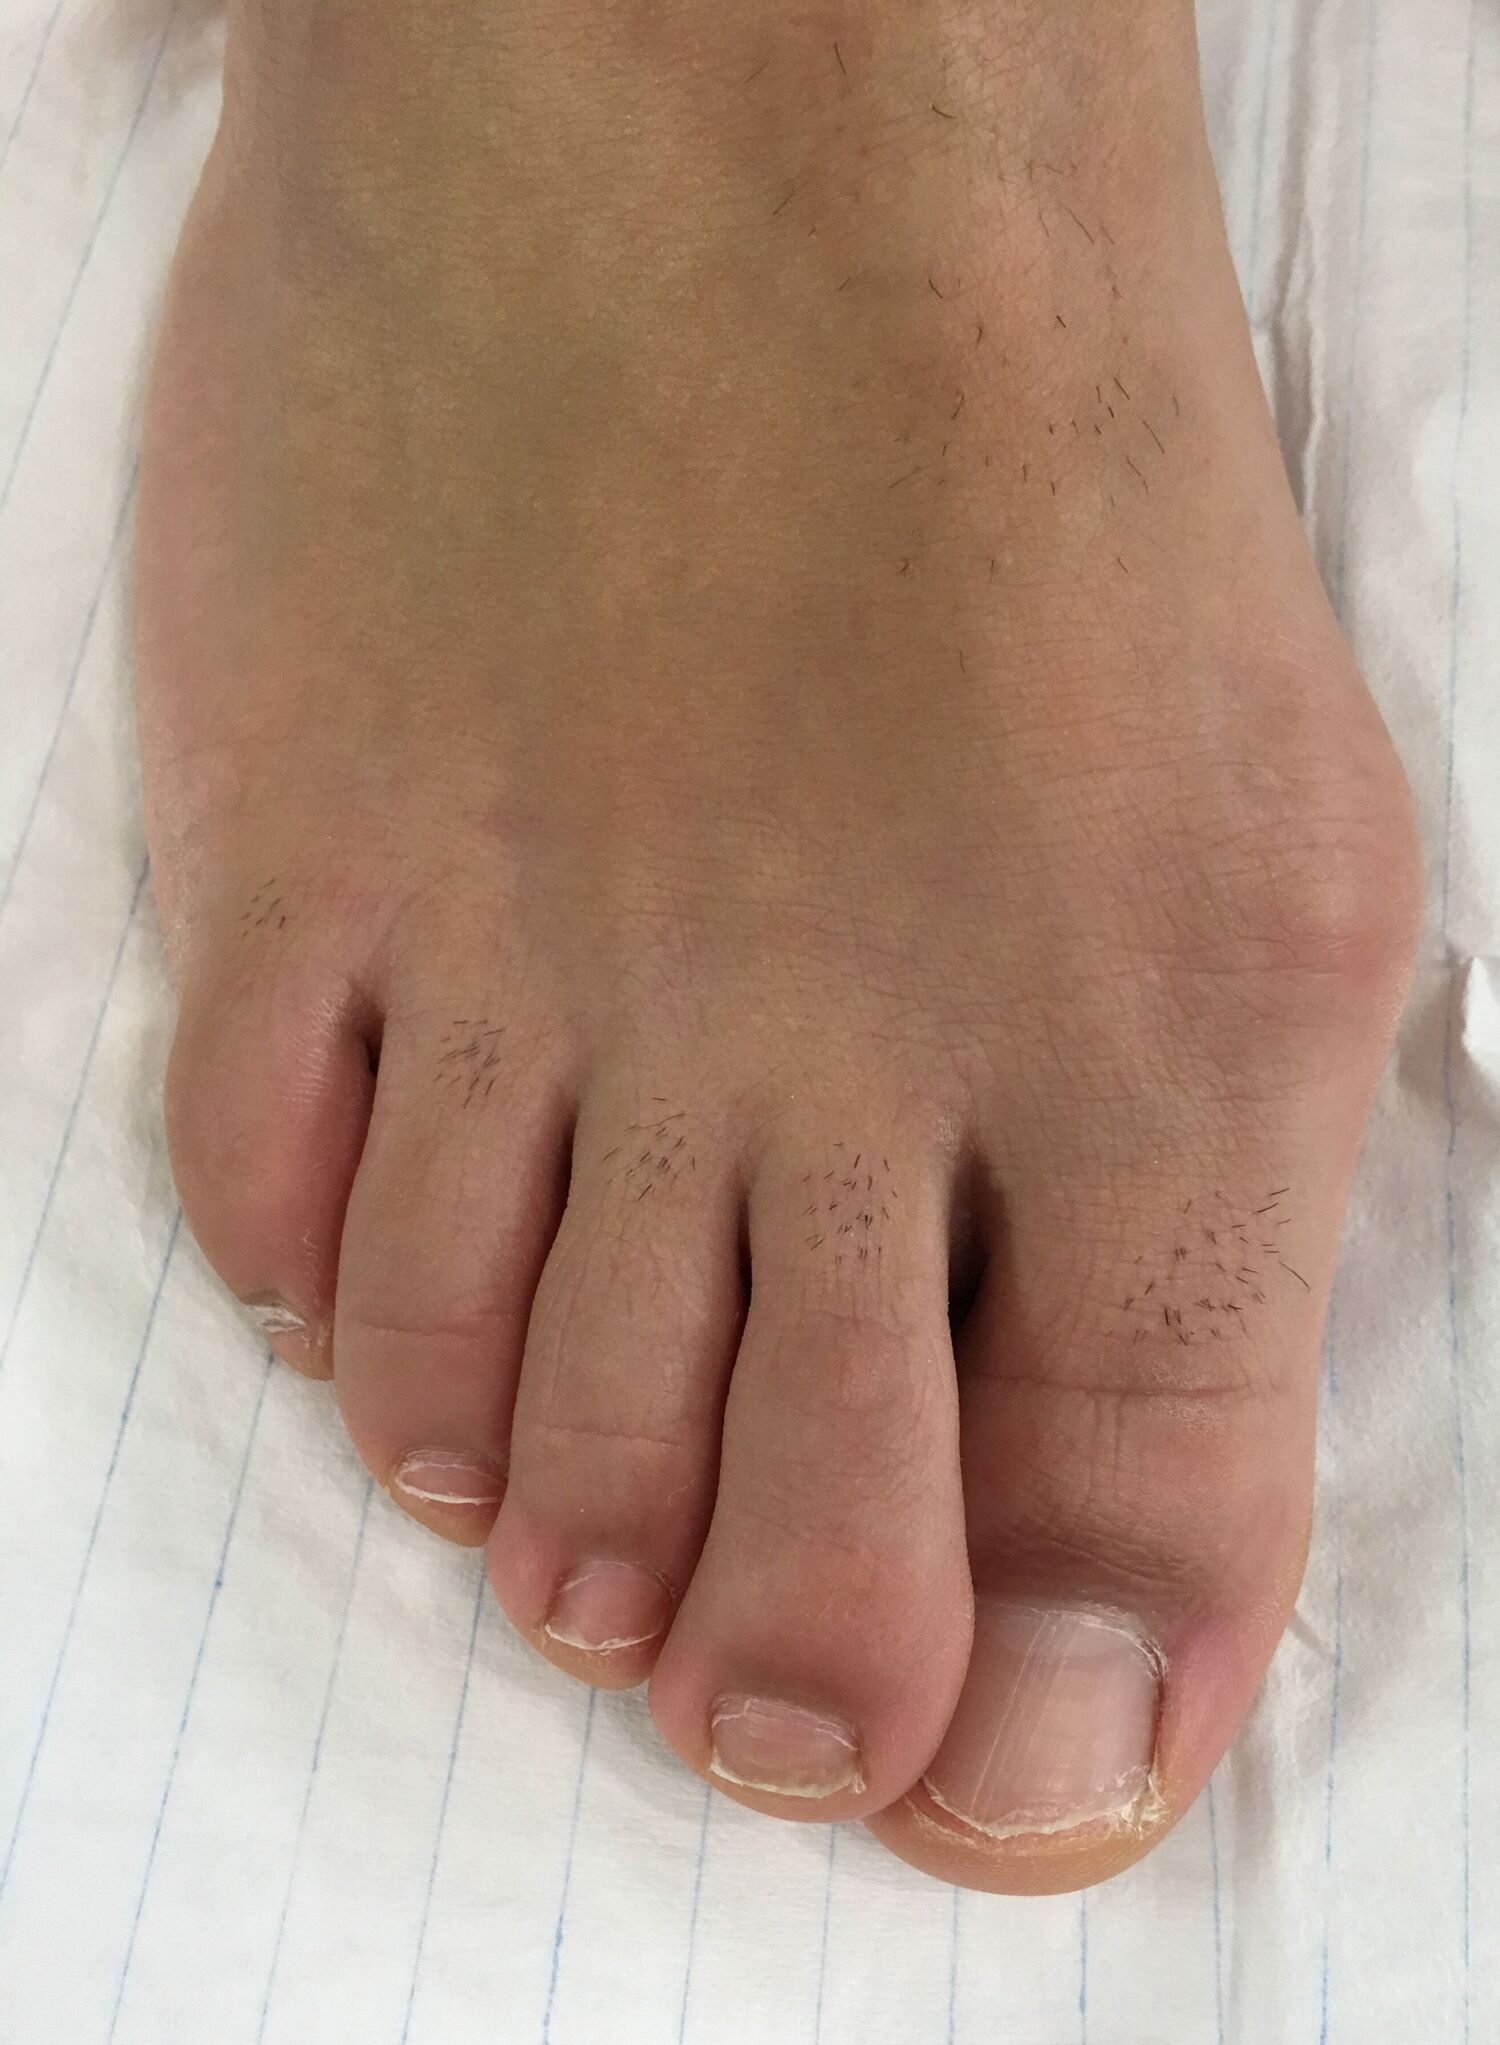

Die Chevron-Osteotomie

Bei geringen Fehlstellungen kann eine Chevron-Osteotomie durchgeführt werden. Zunächst werden die Weichteile, die das Gelenk umgebenden, gelockert. Auf diese Weise wird die Großzehe in eine normale Position gebracht. Nach Abtragung des knöchernen Vorsprunges (Pseudoexostose) im Bereich des 1. Mittelfußknochens kann die knöcherne Fehlstellung korrigiert werden. In korrigierter Stellung wird der Knochen mit einer Schraube fixiert.